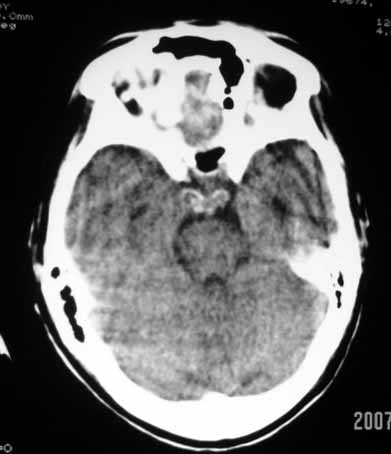

1、右侧外囊区脑软化;

2、左侧额、顶、枕区脑转移瘤。

脑转移瘤

右侧外囊区脑软化